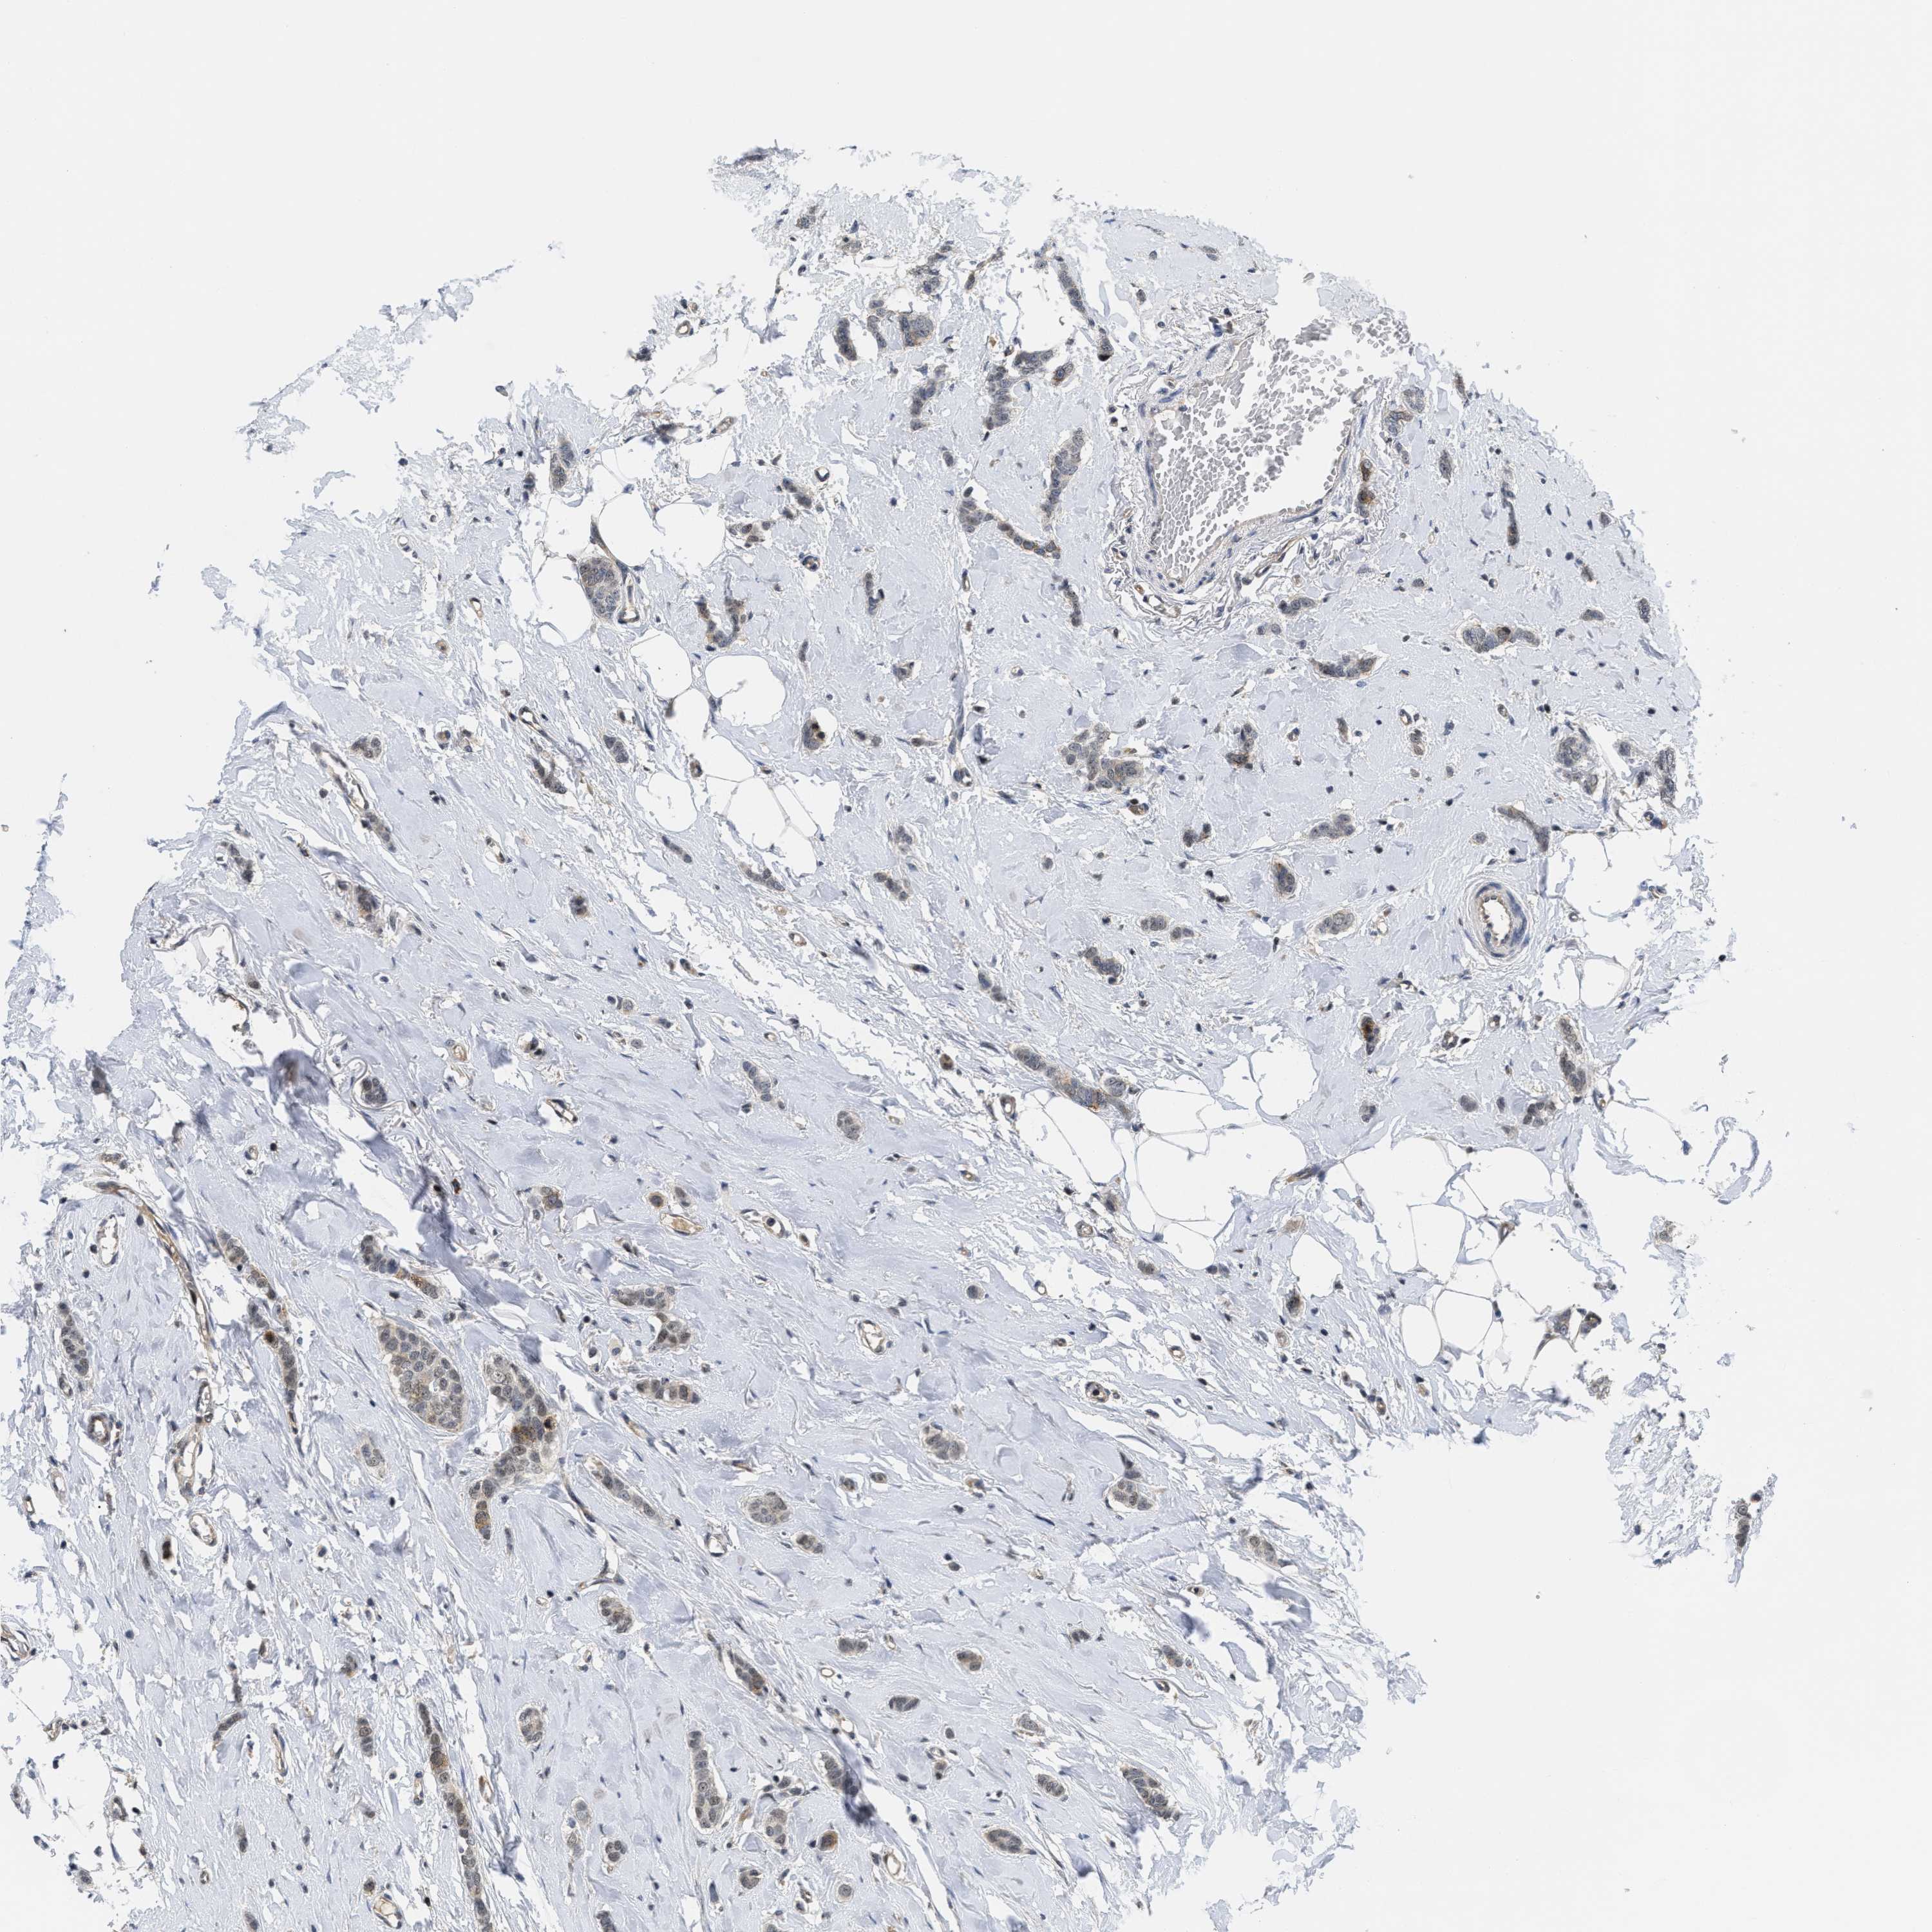

CANCER BREAST CANCER Show tissue menu

BRCA TCGA BRCA VALIDATION PROTEIN EXPRESSION

ANTIBODIES

AND

VALIDATION